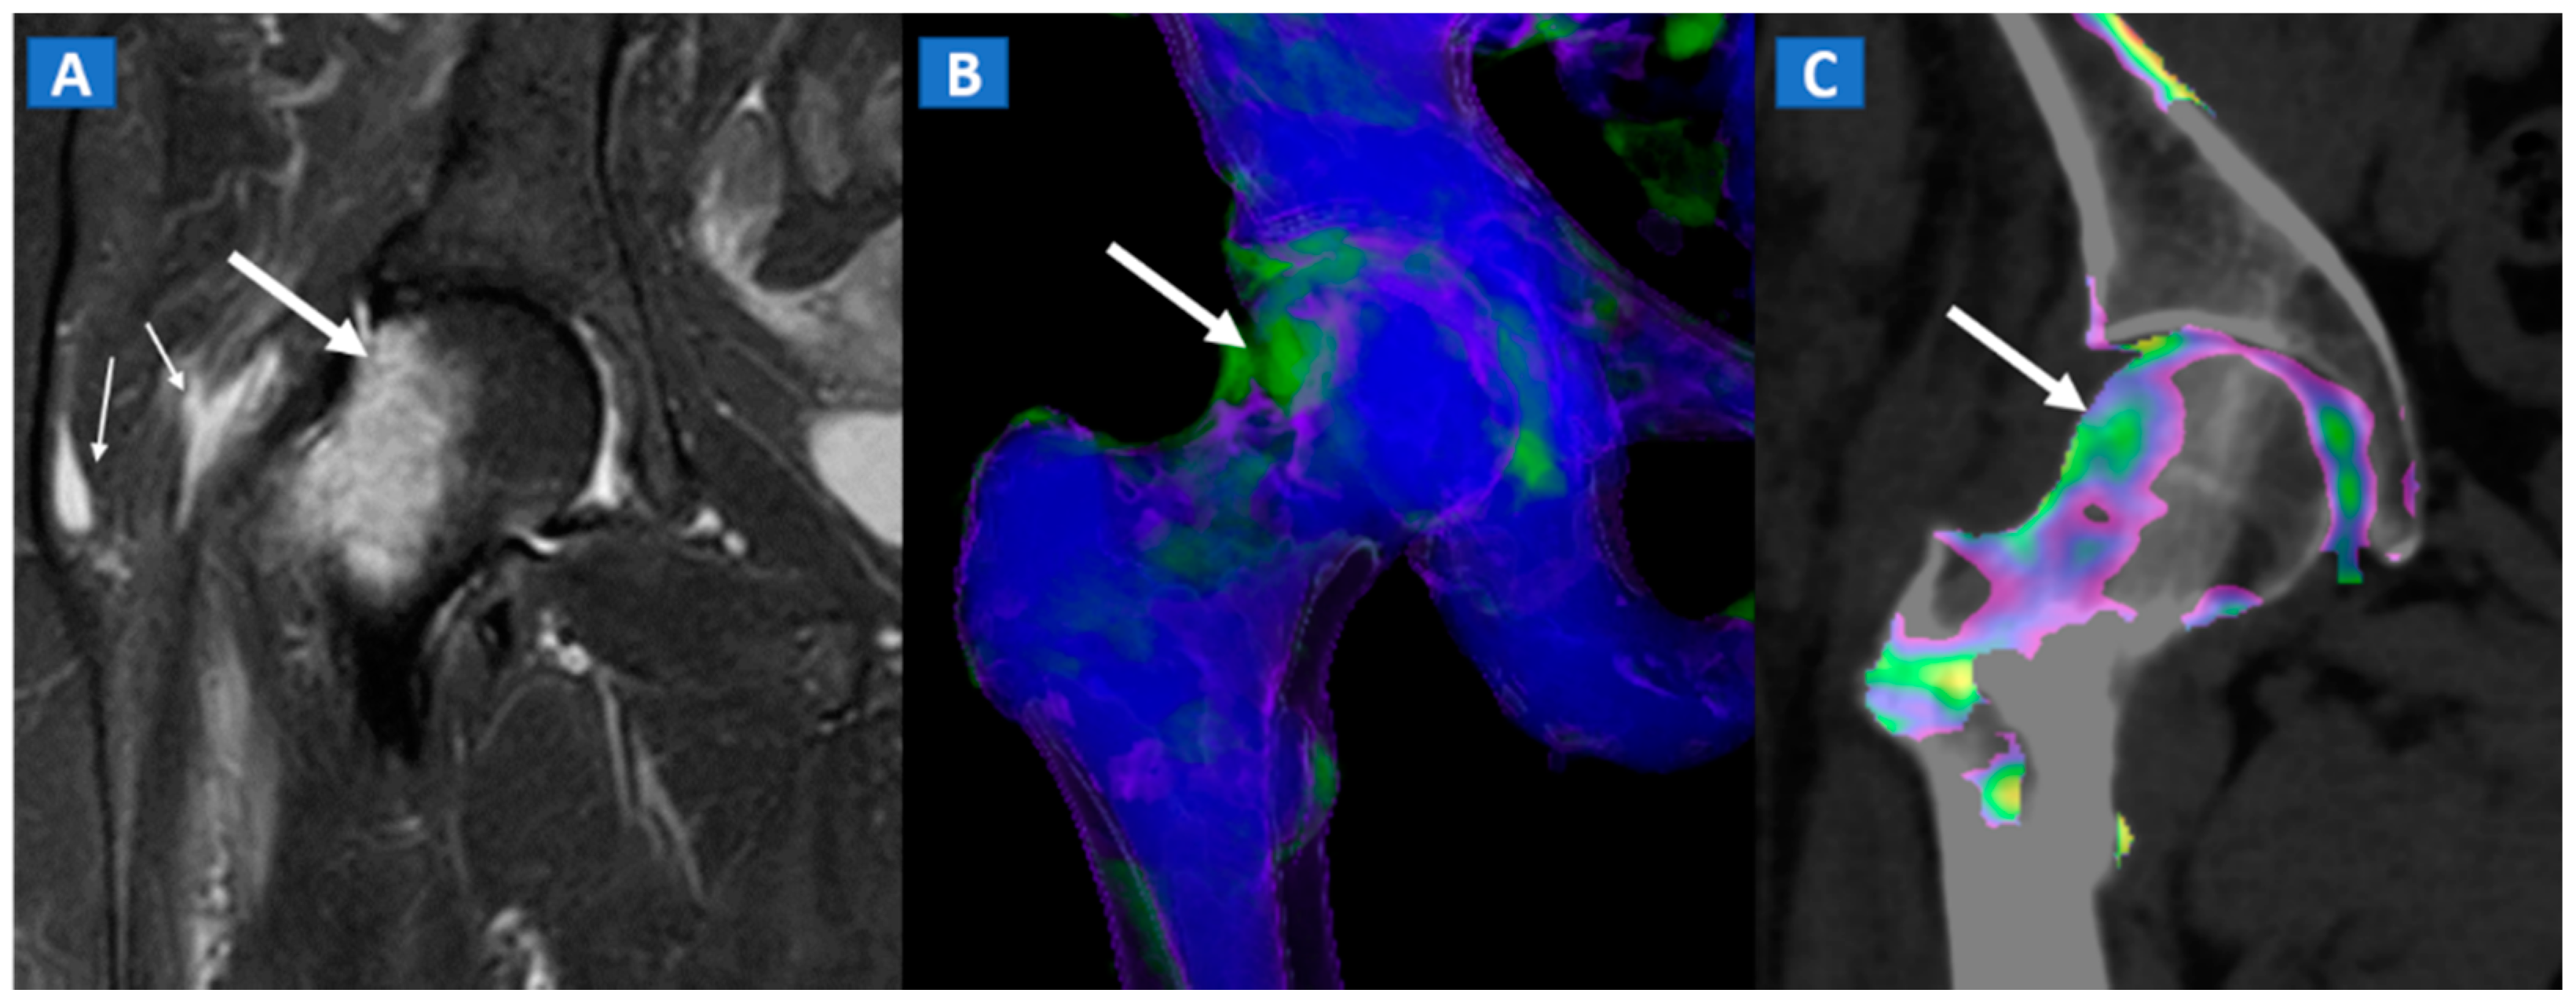

Transient bone marrow oedema syndrome is a self-limiting disease characterized by pain and localized BME, which often affects lower limb joints. Besides confirming the tendency of BME to spare subchondral areas (Figure 6), DECT imaging can also rule out any associated findings to narrow the differential diagnosis. DECT is indeed capable to diagnose stress fractures, early AVN stages, and inflammatory arthropathies.

A 46-year-old female with non-traumatic right hip pain. On the coronal STIR MRI image (A), hyperintense BME of the femoral neck is depicted (thick arrow), sparing the subchondral femoral head area. Note the associated trochanteric bursitis (thin arrows). The pattern of distribution of BME (arrow) is confirmed on the corresponding DECT coronal 3D image (B), and on the 1 mm coronal DECT image (C) (arrow).